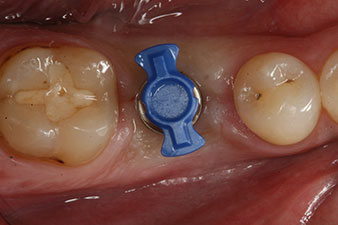

SmartPeg

Fig. 4 : Tiges de mesure SmartPeg vissées pour mesurer les quotients de stabilité de l’implant à l'aide du module W&H Osstell ISQ intégré.

Le couple utilisé pour la pose guidée était de 43 Ncm.

En outre, après avoir vissé une tige de mesure (SmartPeg) spécialement conçue pour l'implant, la valeur ISQ a été mesurée à l’aide de la sonde du module W&H Osstell ISQ.

Ce module est fourni en option avec l’Implantmed de W&H et est fixé au moteur d’implantologie (cf. Fig. 11). La valeur ISQ adimensionnelle mesurée immédiatement après l’insertion était de 64 dans l’axe oro-vestibulaire et de 68 dans l’axe mésio-distal (valeur maximale = 100).

Ces valeurs auraient pu indiquer une cicatrisation ouverte, voire une restauration immédiate. Étant donné le volume osseux crestal insuffisant au niveau de l’implant, une augmentation osseuse a été pratiquée localement à l’aide des fragments osseux recueillis lors de la préparation du lit implantaire, et des points de suture effectués pour éviter le contact de la salive.